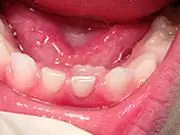

Adult Teeth Coming in Behind Baby Teeth

This is a very common occurrence with children, usually the result of a lower, primary (baby) tooth not falling out when the permanent tooth is coming in. In most cases if the child starts wiggling the baby tooth, it will usually fall out on its own within two months. If it doesn't, then contact your pediatric dentist, where they can easily remove the tooth. The permanent tooth should then slide into the proper place.